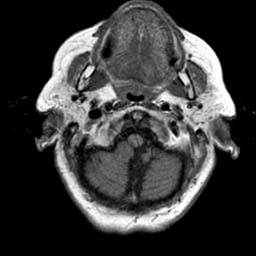

To demonstrate the effectiveness and efficiency of the proposed image fusion method , we conduct a set of comparative experiments on three image datasets. The first is composed by 8 pairs of multi-modal medical images and the second one contains 15 pairs of multi-focus gray or color natural images. These two datasets are often used in many related papers and some examples are shown in Figure 3(a) and Figure 3(b). The third one is a new multi-focus cervical cell image dataset collected by ourselves, which consists of 15 groups of color images and each group contains a series of multi-focus cervix cell images with size of or , etc. Some source examples are shown in Figure 3(c). Our source code implemented in C++ along with the new multi-focus cervical cell image dataset is available online.

We first evaluate the performance of the proposed method under varying total number of octaves and number of layers sampled per octave. The fused images of a pair of multi-modal medical images with different and are shown in Figure 4. In this example, on the one hand, when only 1 or 2 octaves are involved in constructing the DoG pyramid, the fused images fail to keep the integrity information of large size objects (e.g. eyeballs), while by increasing the value of , the integrity information of eyeballs is preserved. On the other hand, although not as significant as the increase of octave numbers , the fused image can contain more details by the increase of layer numbers . The corresponding objective quality metrics are shown in Figure 5. As shown in Figure 5(a), most of the metric values are improved as the number of octaves increases with the fixed layer numbers 3 in the global tendency and each of them tends to be stable when the number of octaves is 5. To get a relatively good quality from Figure 5(b), we can notice that some of the metric values can get a good performance when the number of layers is 3, such as the MI, SSIM, QI and VIF, though there are only a little change of all the metric values by increasing the number of layers with the fixed octave numbers 5. Because it will result in more computation burden with the increase of the value and , and for different kinds of source images, there are different performance with the diverse parameter settings. To get a trade-off between them in our experiments, we set for the multi-modal dataset, for the natural datasets and for the multi-focus cell dataset, respectively.

Figure 6 shows the fused images obtained by different methods with the multi-modal source images shown in Figure 3(a). As shown in these figures, the proposed method can produce images which preserve the complementary information of different source images well. Moreover, due to the scale-invariant structure saliency selection, our method can keep the integrity information of large size objects and the visual details simultaneously. Although the fused image generated by other methods can also capture the details to some extent, all of them fail to keep the integrity information of large size objects such as the eyeballs. Furthermore, from Figure 6(k)-6(t), the DTCWT, GFF, IM and NSCT methods may decrease the brightness and contrast while the proposed method can preserve these features and details without producing visible artifacts and brightness distortions.